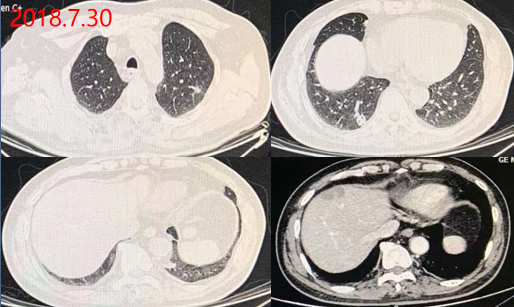

2018.7.30: